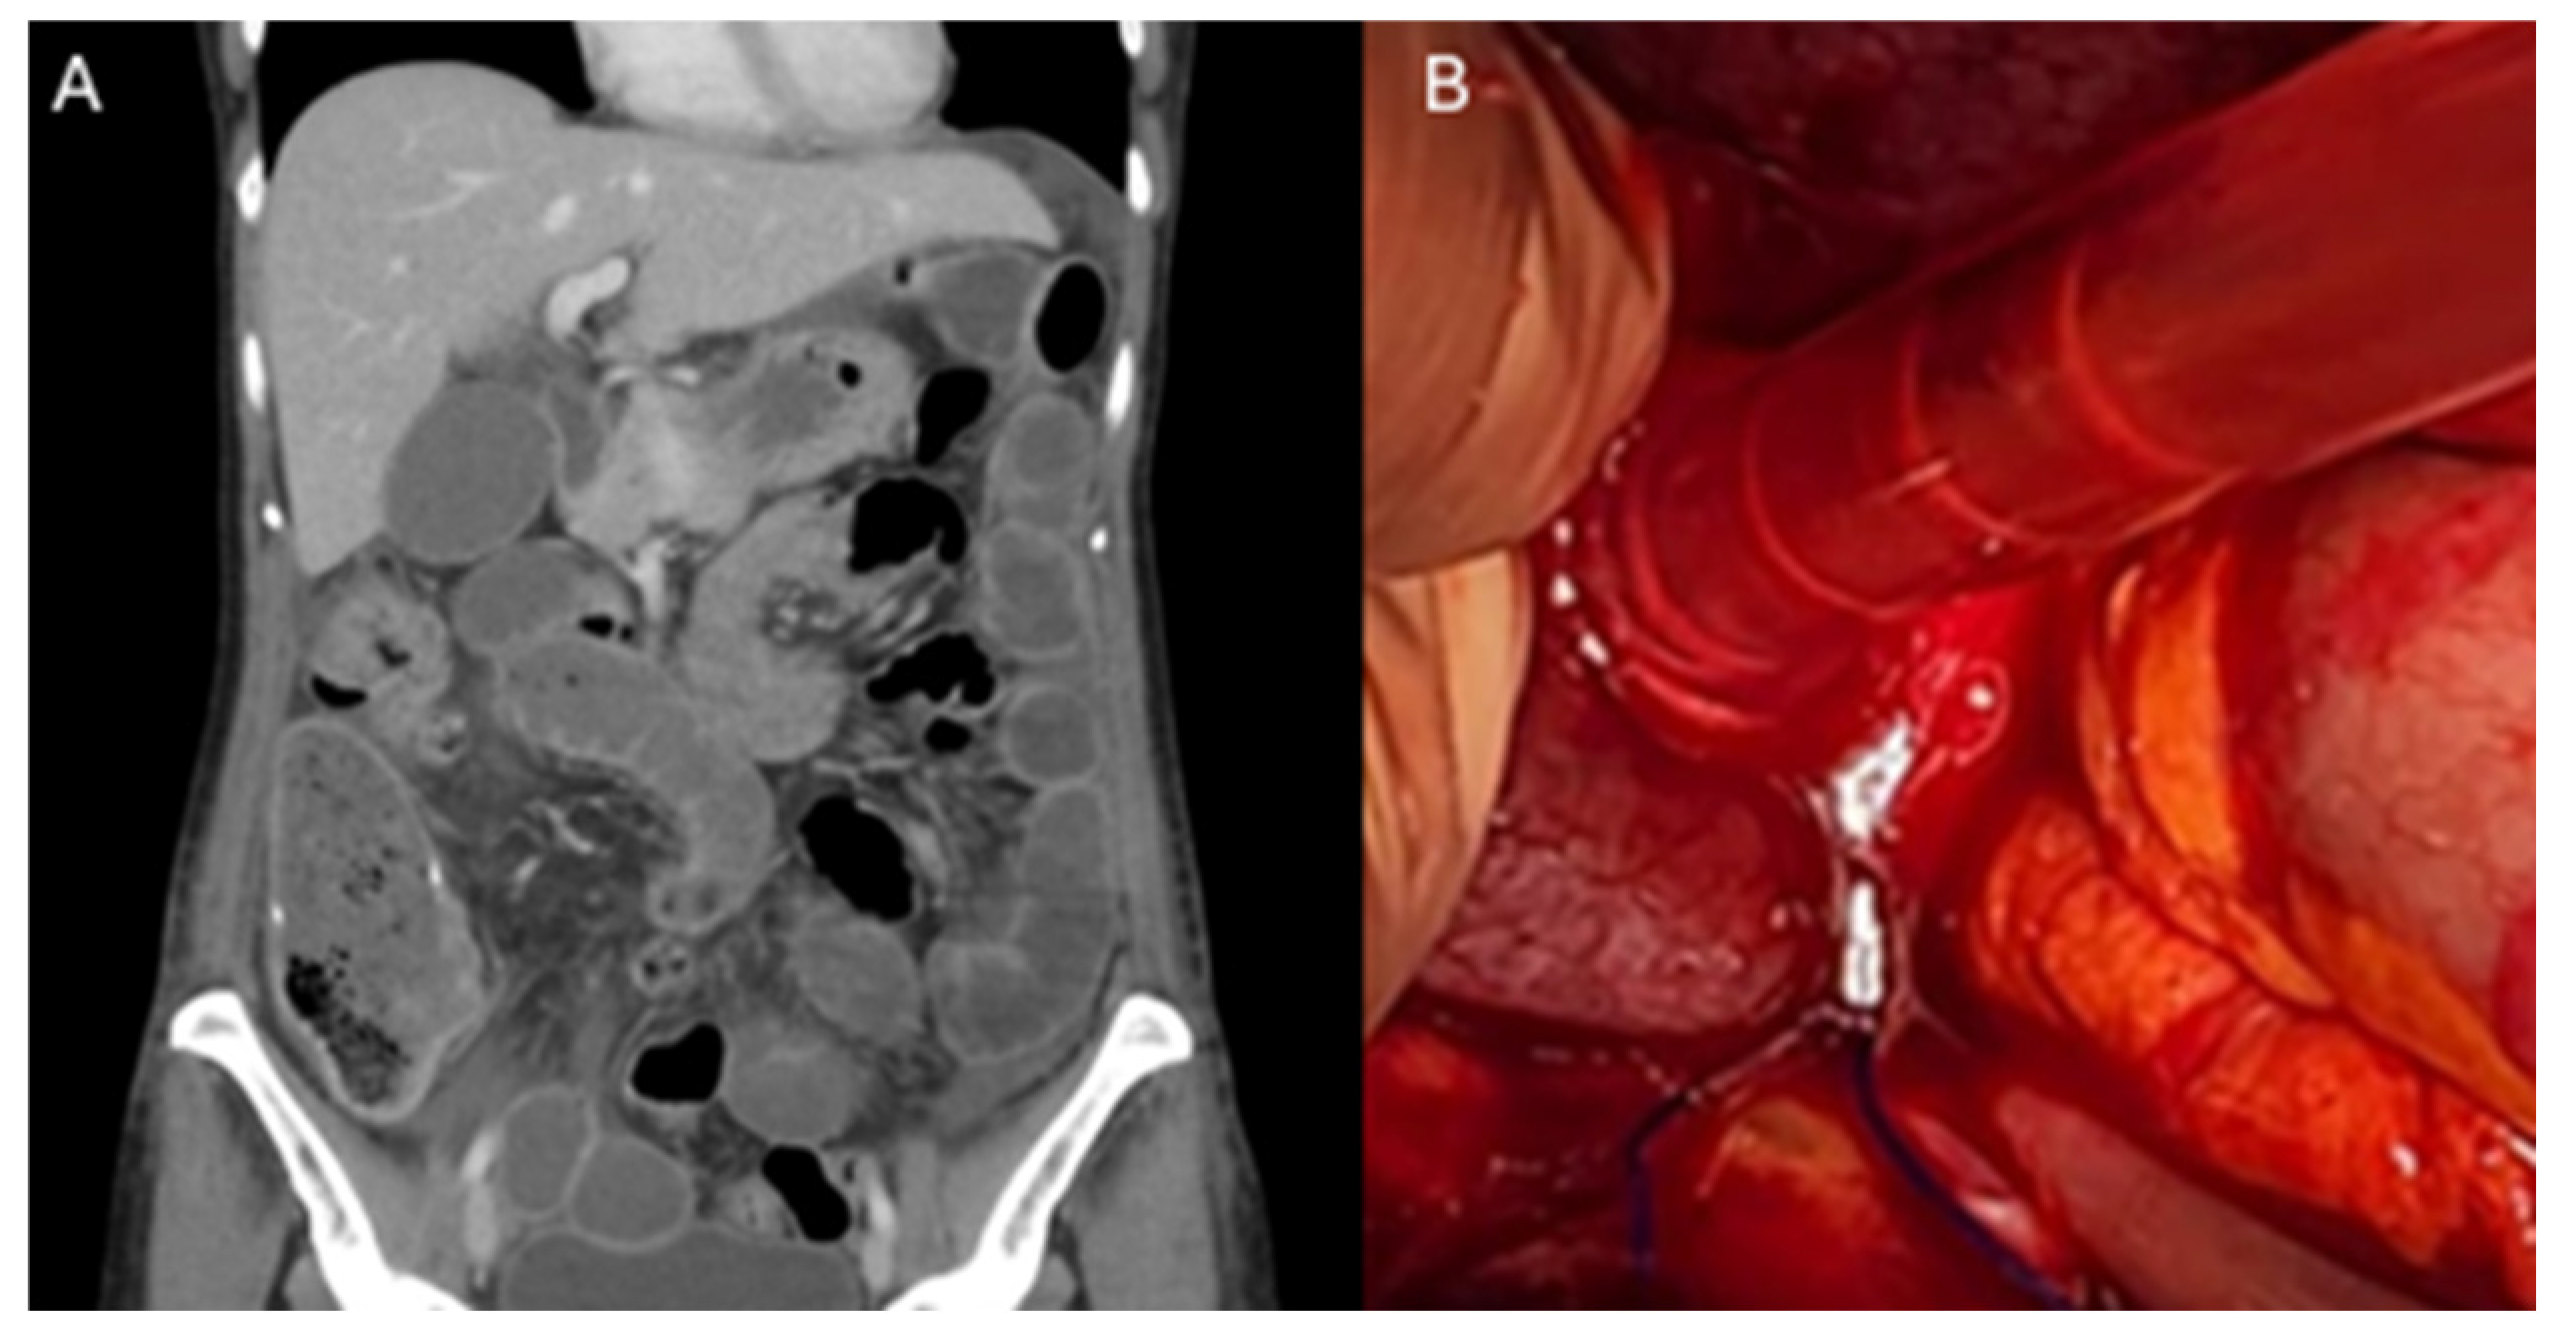

The approach to suspected small bowel obstruction secondary to a barbed suture in most cases was a diagnostic laparoscopy (88%), with only one case describing a diagnostic laparotomy as initial treatment. Intraoperatively, all the cases involved the tail of the barbed suture being adhered to the small bowel, causing small bowel obstruction (Figure 2B). Two cases reported progression of the entangled bowel to the ischaemic bowel, requiring resection. The fatty appendages of the sigmoid colon were also found to be adherent to the barbed suture tail in 25% of cases. Most cases were resolved with truncation/removal of the implicated barbed suture tail (63%). Two cases required additional small bowel resection. The average length of stay during these cases was 6 days (median 4 days), with a range from 2 to 18 days (Table 1).

Figure 2.

Small bowel obstruction secondary to entanglement in a barbed suture tail. (A) Coronal section of Computed Tomography scan of the Abdomen and Pelvis (CTAP), demonstrating distended loops of small bowel secondary to entanglement in a barbed suture tail in the pelvis. (B) Intraoperative finding of distended loops of small bowel anchored in the pelvis secondary to entanglement with a barbed suture tail.

Imaging in this subgroup of patients with Computed Tomography scans of the Abdomen and Pelvis (CTAP) typically demonstrates distension of the small bowel (Figure 2A); however, this may also appear as a volvulus. The barbed suture tail can act as a fixed point for the bowel to rotate around, creating a volvulus and potentially leading to ischaemia. CT scan findings in these cases have been found to often accurately correlate with intraoperative findings.